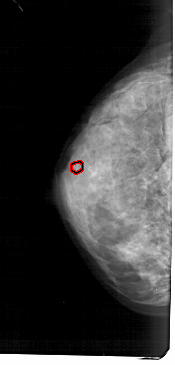

A_1684_1.LEFT_CC

FILE: A_1684_1.LEFT_CC.OVERLAY

TOTAL_ABNORMALITIES 1

ABNORMALITY 1

LESION_TYPE CALCIFICATION TYPE PLEOMORPHIC DISTRIBUTION CLUSTERED

ASSESSMENT 4

SUBTLETY 2

PATHOLOGY BENIGN

TOTAL_OUTLINES 1

BOUNDARY